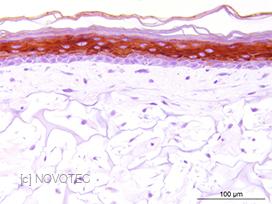

Novotec a également collaboré à l'étude de la biocompatibilité et de la dégradation de biomatériaux. Après implantation ou injection de ces biomatériaux dans la peau (pansements, dermal fillers résorbables/permanents...), des colorations standards (HES, Trichrome Masson Goldner) et spécifiques (MGG) sur tissus inclus en paraffine ou en résine méthylmétacrylate (MMA) sont réalisées. Des analyses par des méthodes qualitative et semi-quantitative permettent d'évaluer la dégradation des biomatériaux et la réaction inflammatoire.